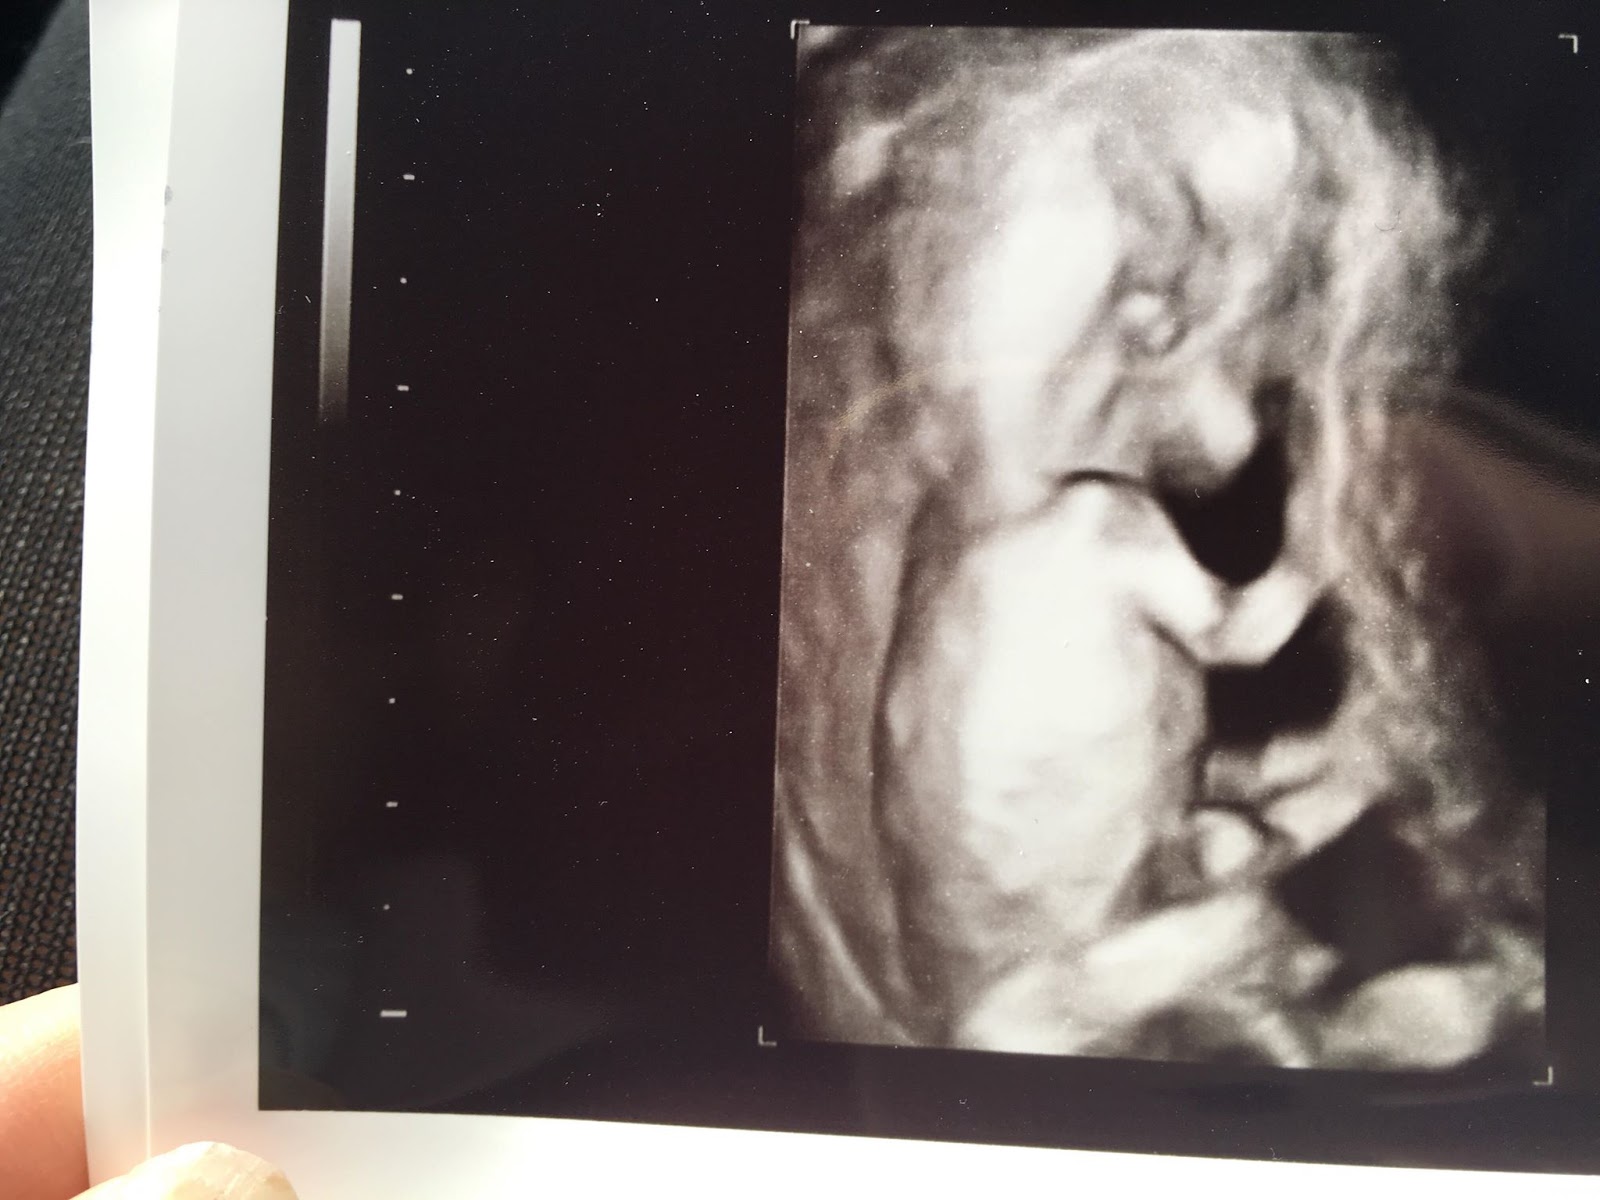

Perjantaina oli meidän np ultra. Vauva oli kasvanut ihan kamalasti ja se oli jo ihan ihka oikean vauvan näköinen. Mua jännitti tosi paljon, mietin jopa että olisi tehnyt mieli perua koko ultra. Viimein kun pääsimme huoneeseen oli vastassa aika kylmän oloinen kätilö. Tämä oli niin liukuhihnatyötä hänelle, mutta en antanut sen lannistaa. Kyyneleen valuivat poskillani kun vauvamme ilmestyi näytölle. Ensin hän oli hyvin rauhallisesti siellä, että saimme otettua mitat hyvin. Sitten kätilö alkoi herättelemään ja siellä se pieni ihme sätki oikein kunnolla :D

Kätilö ei saanut mitattua kunnolla niskaturvostusta ja sanoi että ultrataan vielä alakautta. Mua rupes naurattaan ja sanoin että apua en oo varautunut tähän :D Sieltä kautta onnistui ja niskaturvotus oli 0,5. Vauvan syke oli 164.

Kuvissa pieni ihmeemme pitkine koipineen :D <3